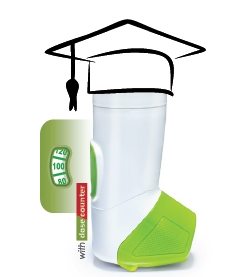

A new revolutionary inhaler called Synchrobreathe (SB) was launched recently.

SB is very simple to use, 3 easy steps. By putting the SB inhaler in your mouth and breathing in slowly, you will trigger it to release the medication.

SB also contains a dose counter which allows you to track the doses remaining in the inhaler. This will remind you when it is time to get your new inhaler.

SB is very simple to use, 3 easy steps. By putting the SB inhaler in your mouth and breathing in slowly, you will trigger it to release the medication.

SB also contains a dose counter which allows you to track the doses remaining in the inhaler. This will remind you when it is time to get your new inhaler.